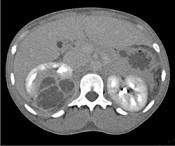

问题 一女性患者,一月前出现尿频、尿急等症状为引起注意,现有高热,阅图后最可能的诊断为 ( )

选项 A.急性肾盂肾炎 B.肾脓肿 C.多囊肾 D.肾结核 E.肾癌

答案 B